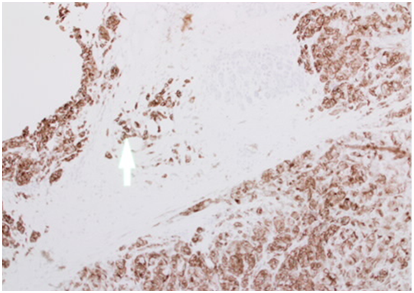

A 43years old white premenopausal female patient admitted though Emergency Department with a recent history of unwell feeling in addition to sudden onset of dizziness, ataxia, vomiting & loss of vision on right eye. Initial clinical assessment revealed loss of coordination, as well as blind right eye and partial unilateral deafness. The patient partner pointed to a smaller pigmented nevus in the anterior chest wall which started to be darker recently. Clinically, there is bilateral indeterminate scattered breast modularity and a small breast lump at the outer upper quadrant of the right breast measures about 30mm. Mammogram and breast US showed bilateral scattered irregular hypo echoic suspicious lesions measures between 5mm & 20mm , graded as M4U4. [BI-RADS: Breast Imaging Reporting and Data System]. A core biopsy was taken from the largest lesion in the right breast (Figure 1) (Figure 2).

Figure 1 A: CC View, B: MLO View.

CC (Cranial-Caudal) & MLO (Medio-lateral-oblique) views of right mammogram indicating 17mm suspicious lesion in the OUQ (Outer Upper Quadrant).